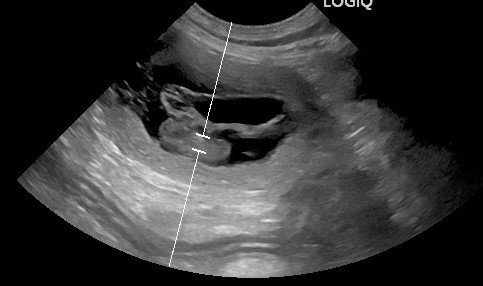

Wir freuen uns riesig, bekanntgeben zu dürfen, dass unsere geliebte "Prinzessin" Maisha tragend ist. Der gestrige Ultraschall (27.01.) hat es bestätigt.

Wir erwarten aus der Verpaarung von Jupp und Maisha Anfang März zauberhafte Welpen 🎉!